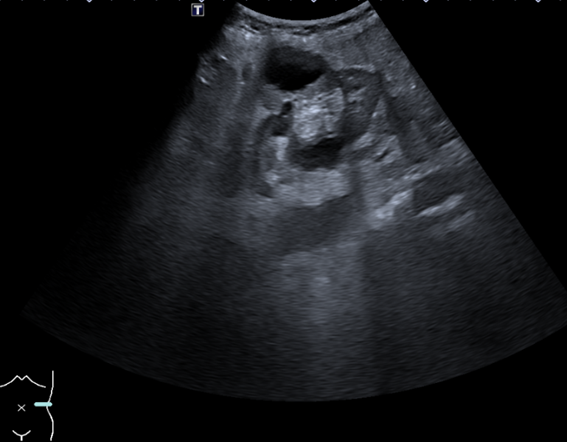

Ante la persistencia de los síntomas, se realiza ecografía en Atención Primaria, identificándose una lesión ovalada de unos 9 cm adyacente al riñón izquierdo, heterogénea, con áreas quísticas y sin flujo Doppler. La revisión de imágenes antiguas revela un quiste simple de gran tamaño en la misma localización, por lo que se sospecha complicación del mismo. Se deriva a Medicina Interna para estudio.